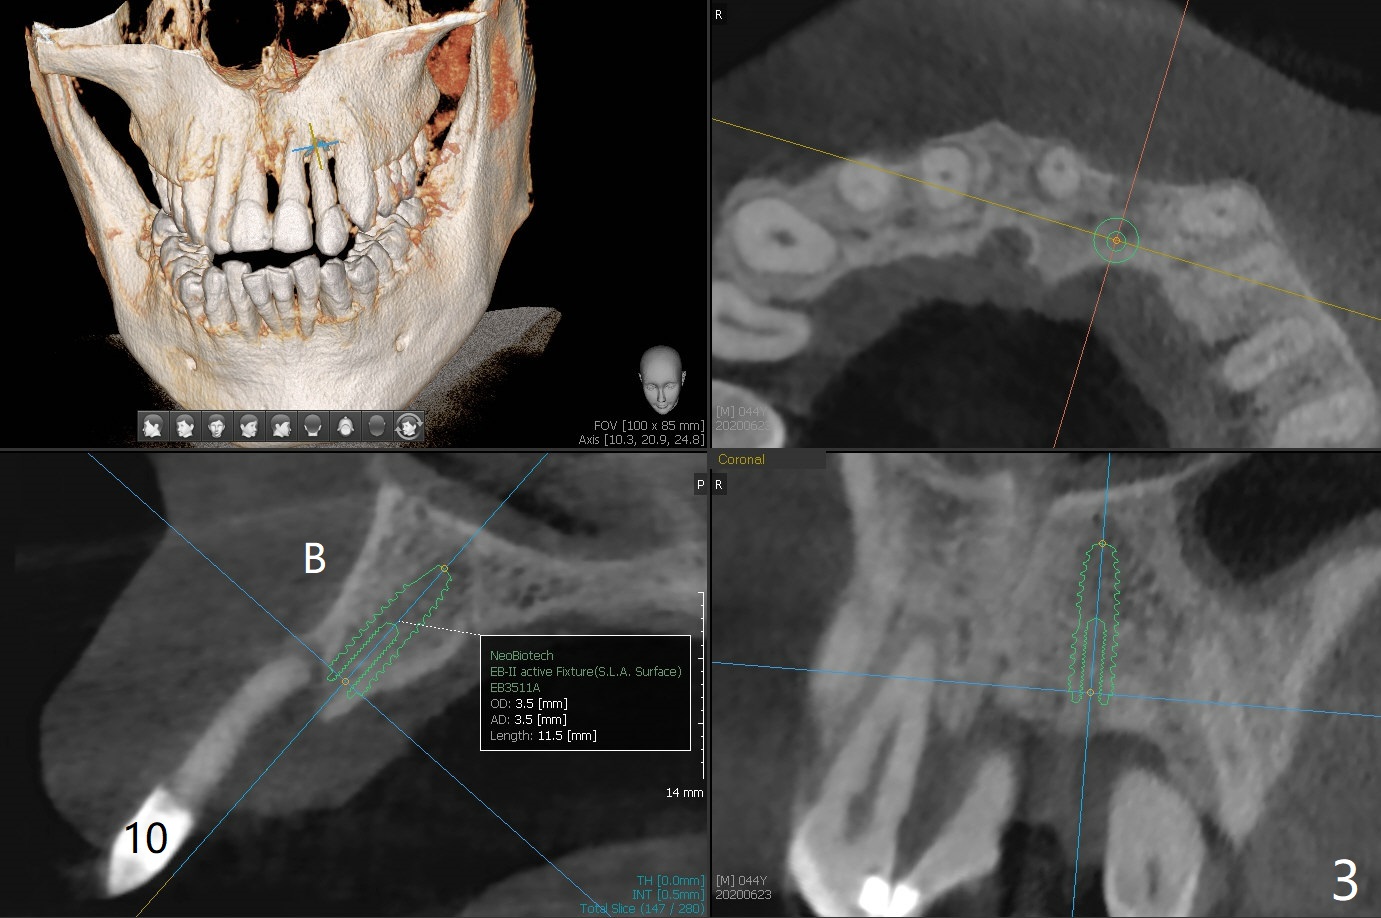

A 44-year-old man with generalized periodontitis (Fig.1) will return to clinic for #10 extraction (Fig.2) prior to brain tumor removal. Immediate implant (Fig.3) or not, sticky bone will be placed on the root surface of the neighboring teeth (Fig.4 red circles) after SRP. Place PRF membrane as early as possible, e.g, buccal, to avoid waste.